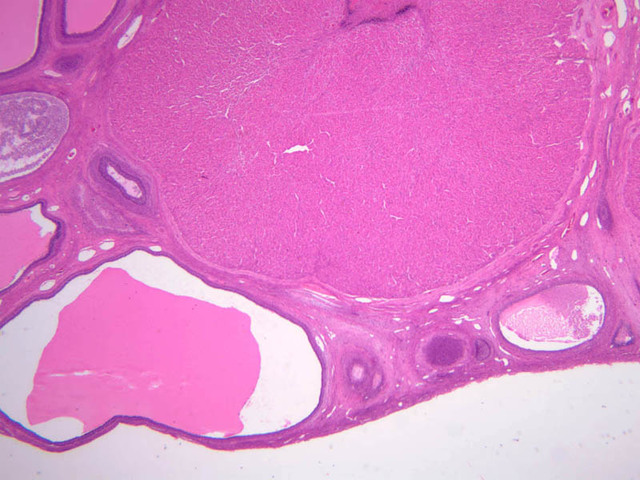

The ovary is a somewhat oval and slightly flattened organ situated near the fimbriated end of the uterine tube (B-94, monkey ovary, H&E [1x, 1x]; B-95, monkey ovary, H&E [1x-labeled, 1x]; B-96, monkey ovary and tube, H&E [1x]; B-54, H&E [1x, 1x]). Its exposed surface is covered by a mesothelial sheet of squamous or cuboidal epithelium. Just deep to this is an ill defined area of dense fibrous connective tissue referred to as the tunica albuginea (B-96 [2.5x-labeled, 10x-labeled, 20x, 40x]).

The ovary has two major regions – the cortex and the medulla. The cortex is the broad peripheral area containing follicles in various stages of development, whereas the medulla is the more central area displaying profiles of large blood vessels. These blood vessels gain entrance via the mesovarium. The division between the cortex and medulla is indistinct. In the cortex, stromal cells occupy the areas between the follicles. These cells are closely packed, fusiform (spindle shaped), and have the potential to differentiate into a specialized component of the maturing follicle (theca folliculi).

Corpus Luteum

After rupture of the Graafian follicle, the walls collapse and become folded. Thus, strands of tissue from the theca interna penetrate, to some extent, the mass of granulosa cells. Bleeding from the theca interna may form a blood clot in the antrum. The majority of the cells of the corpus luteum are derived from the granulosa cells. Both the granulosa cells and the cells of the theca interna enlarge and accumulate lipid, thus becoming lutein cells. There are two types of lutein cells - granulosa lutein cells that have a large, vesicular nucleus and vacuolate cytoplasm, and theca lutein cells that are distinguished by smaller darker nuclei. Corpus Luteum (slide B-54, human ovary, H&E [1x-labeled, 2.5x, 10x, 20x, 40x-labeled] [1x-labeled, 1x, 2.5x] [1x, 1x, 1x] 1x, 2.5x, 10x]; B-95, H&E [2.5x])